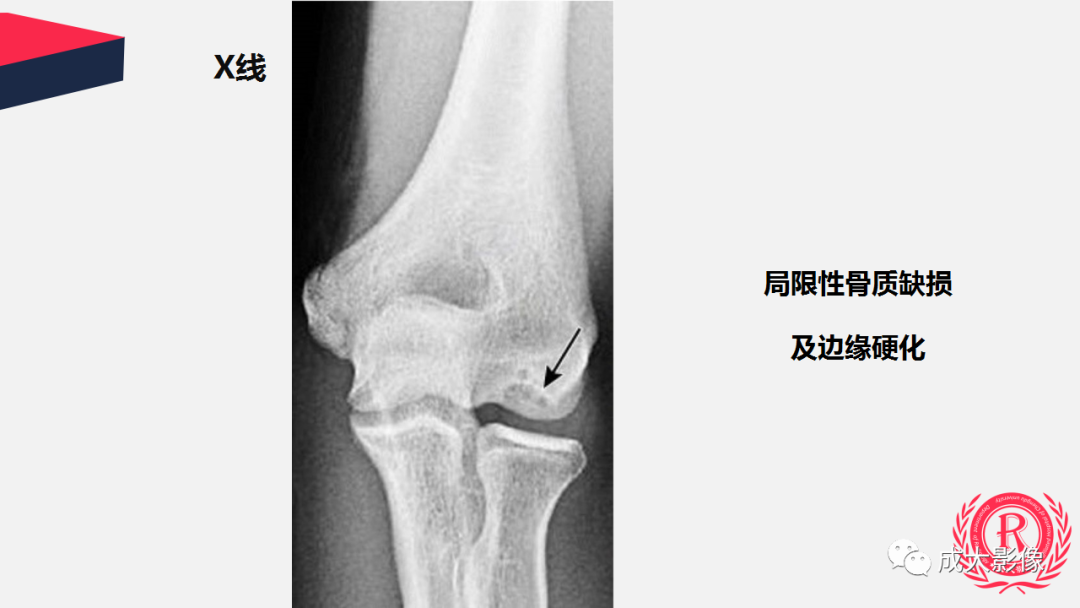

【PPT】剥脱性骨软骨炎-8

【PPT】剥脱性骨软骨炎-9